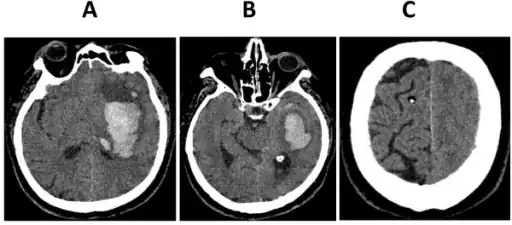

Subfalcine herniation on CT

In cingulate or subfalcine herniation, the most common type, the innermost part of the frontal lobe is scraped under part of the falx cerebri, the dura mater at the top of the head between the two hemispheres of the brain.[7][12] Cingulate herniation can be caused when one hemisphere swells and pushes the cingulate gyrus by the falx cerebri.[5] This does not put as much pressure on the brainstem as the other types of herniation, but it may interfere with blood vessels in the frontal lobes that are close to the site of injury (anterior cerebral artery), or it may progress to central herniation.[7] Interference with the blood supply can cause dangerous increases in ICP that can lead to more dangerous forms of herniation.[13] Symptoms for cingulate herniation are not well defined.[13] Usually occurring in addition to uncal herniation, cingulate herniation may present with abnormal posturing and coma.[5] Cingulate herniation is frequently believed to be a precursor to other types of herniation.[13]